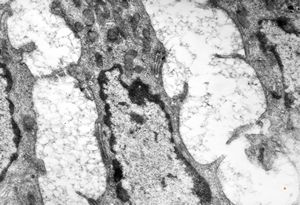

jejunum … lipid malabsorption

M,29y. | jejunum - lipid malabsorption